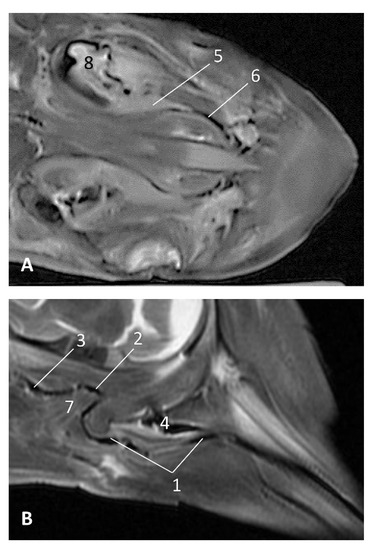

The MRI sagittal images show a pharyngeal cavity in a Globicephala melas fetus (gma1) and we could appreciate the oropharynx (fauces), the nasopharynx and the oesophageal vestibule hypointense in both T1 and T2 sequences(Figure 25A,B). Coronal T1 and T2 sequences show the piriform recess alongside the larynx (Figure 25C,D).

Figure 25. Images of the oral and pharyngeal cavity. MR sagittal and coronal images are oriented so that the rostral is to the right. (A) T1 SE sagittal, (B) T2 FrFSE sagittal, (C) T1 SE coronal and (D) T2 FrFSE coronal planes. 5 months, gma1. 1, Hard palate; 2, Tongue; 3, Oral cavity (closed); 4, Oropharynx: fauces; 5, Oropharynx: soft palate; 6, Laryngopharynx: left piriform recess; 7, Laryngopharynx: oesophageal vestibule; 8, Epiglottis cartilage; 9, Epiglottic vallecula; 10, Arytenoid cartilages; 11, Nasopharynx; 12, Larynx.